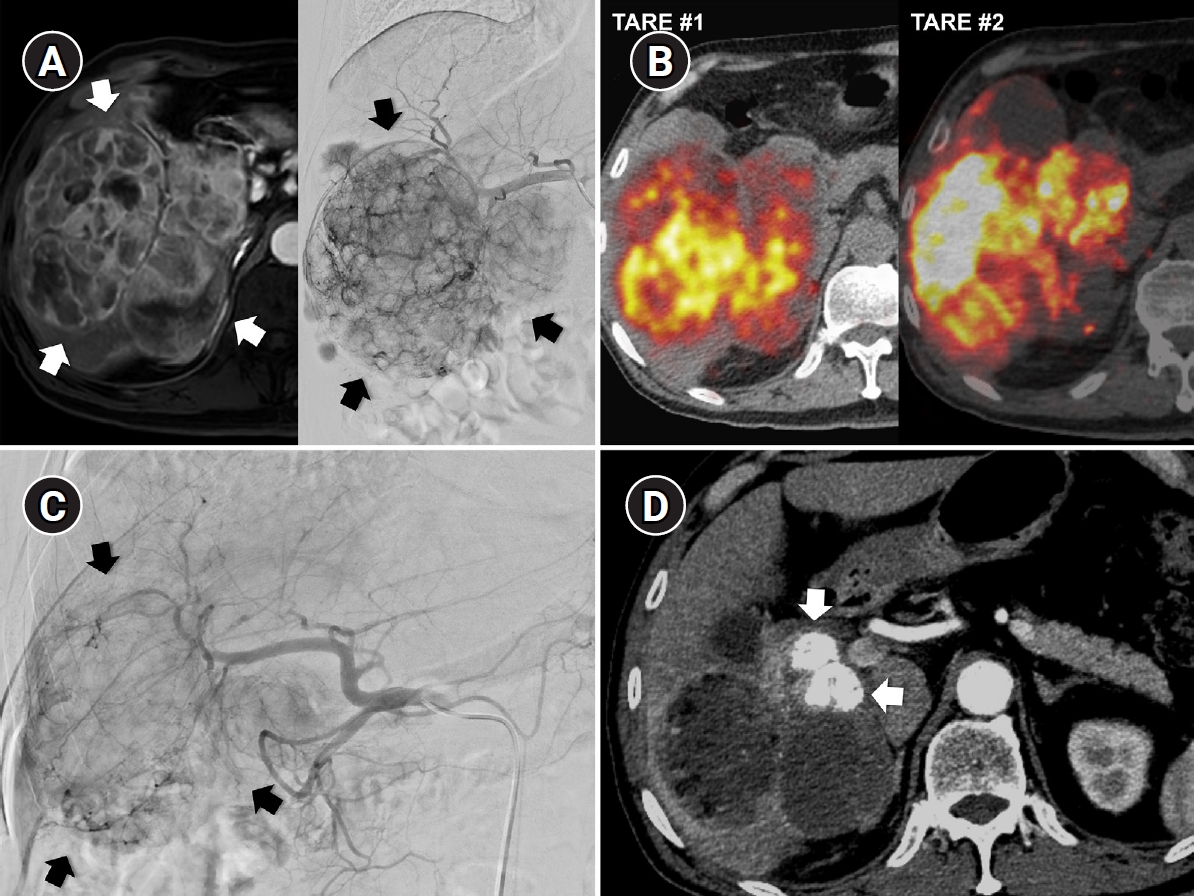

Fig. 6.

Sequential transarterial radioembolization (TARE) followed by transarterial chemoembolization (TACE) in a 77-year-old man with large hepatocellular carcinoma. (A) Magnetic resonance imaging and angiography show a 12.5-cm conglomerated mass (arrows) with multiple satellite nodules in segments 5, 6, and 7. (B) Sequential TARE was planned because a single session could not achieve sufficient tumor dose owing to lung dose limitation. In TARE #1 (5.0 GBq resin microspheres), perfused liver dose was 178 Gy and lung dose was 9.6 Gy. In TARE #2 (5.5 GBq resin microspheres), perfused liver dose was 255 Gy and lung dose was 12.2 Gy. Post-treatment Y-90 positron emission tomography/computed tomography demonstrates heterogeneous intratumoral Y-90 activity in the tumors. (C) Angiography 5 months after TARE #2 shows decreased tumor staining (arrows) in the right lobe. TACE was performed through multiple subsegmental branches supplying residual tumor. (D) After two additional TACE sessions (not shown), the computed tomography obtained 2 years after the initial TARE showed decreased tumor size, near-complete disappearance of arterial enhancement, and partial lipiodol uptake (arrows) in the tumor.

kjir-2025-00066f6.jpg

Fig. 6. Sequential transarterial radioembolization (TARE) followed by transarterial chemoembolization (TACE) in a 77-year-old man with large hepatocellular carcinoma. (A) Magnetic resonance imaging and angiography show a 12.5-cm conglomerated mass (arrows) with multiple satellite nodules in segments 5, 6, and 7. (B) Sequential TARE was planned because a single session could not achieve sufficient tumor dose owing to lung dose limitation. In TARE #1 (5.0 GBq resin microspheres), perfused liver dose was 178 Gy and lung dose was 9.6 Gy. In TARE #2 (5.5 GBq resin microspheres), perfused liver dose was 255 Gy and lung dose was 12.2 Gy. Post-treatment Y-90 positron emission tomography/computed tomography demonstrates heterogeneous intratumoral Y-90 activity in the tumors. (C) Angiography 5 months after TARE #2 shows decreased tumor staining (arrows) in the right lobe. TACE was performed through multiple subsegmental branches supplying residual tumor. (D) After two additional TACE sessions (not shown), the computed tomography obtained 2 years after the initial TARE showed decreased tumor size, near-complete disappearance of arterial enhancement, and partial lipiodol uptake (arrows) in the tumor.